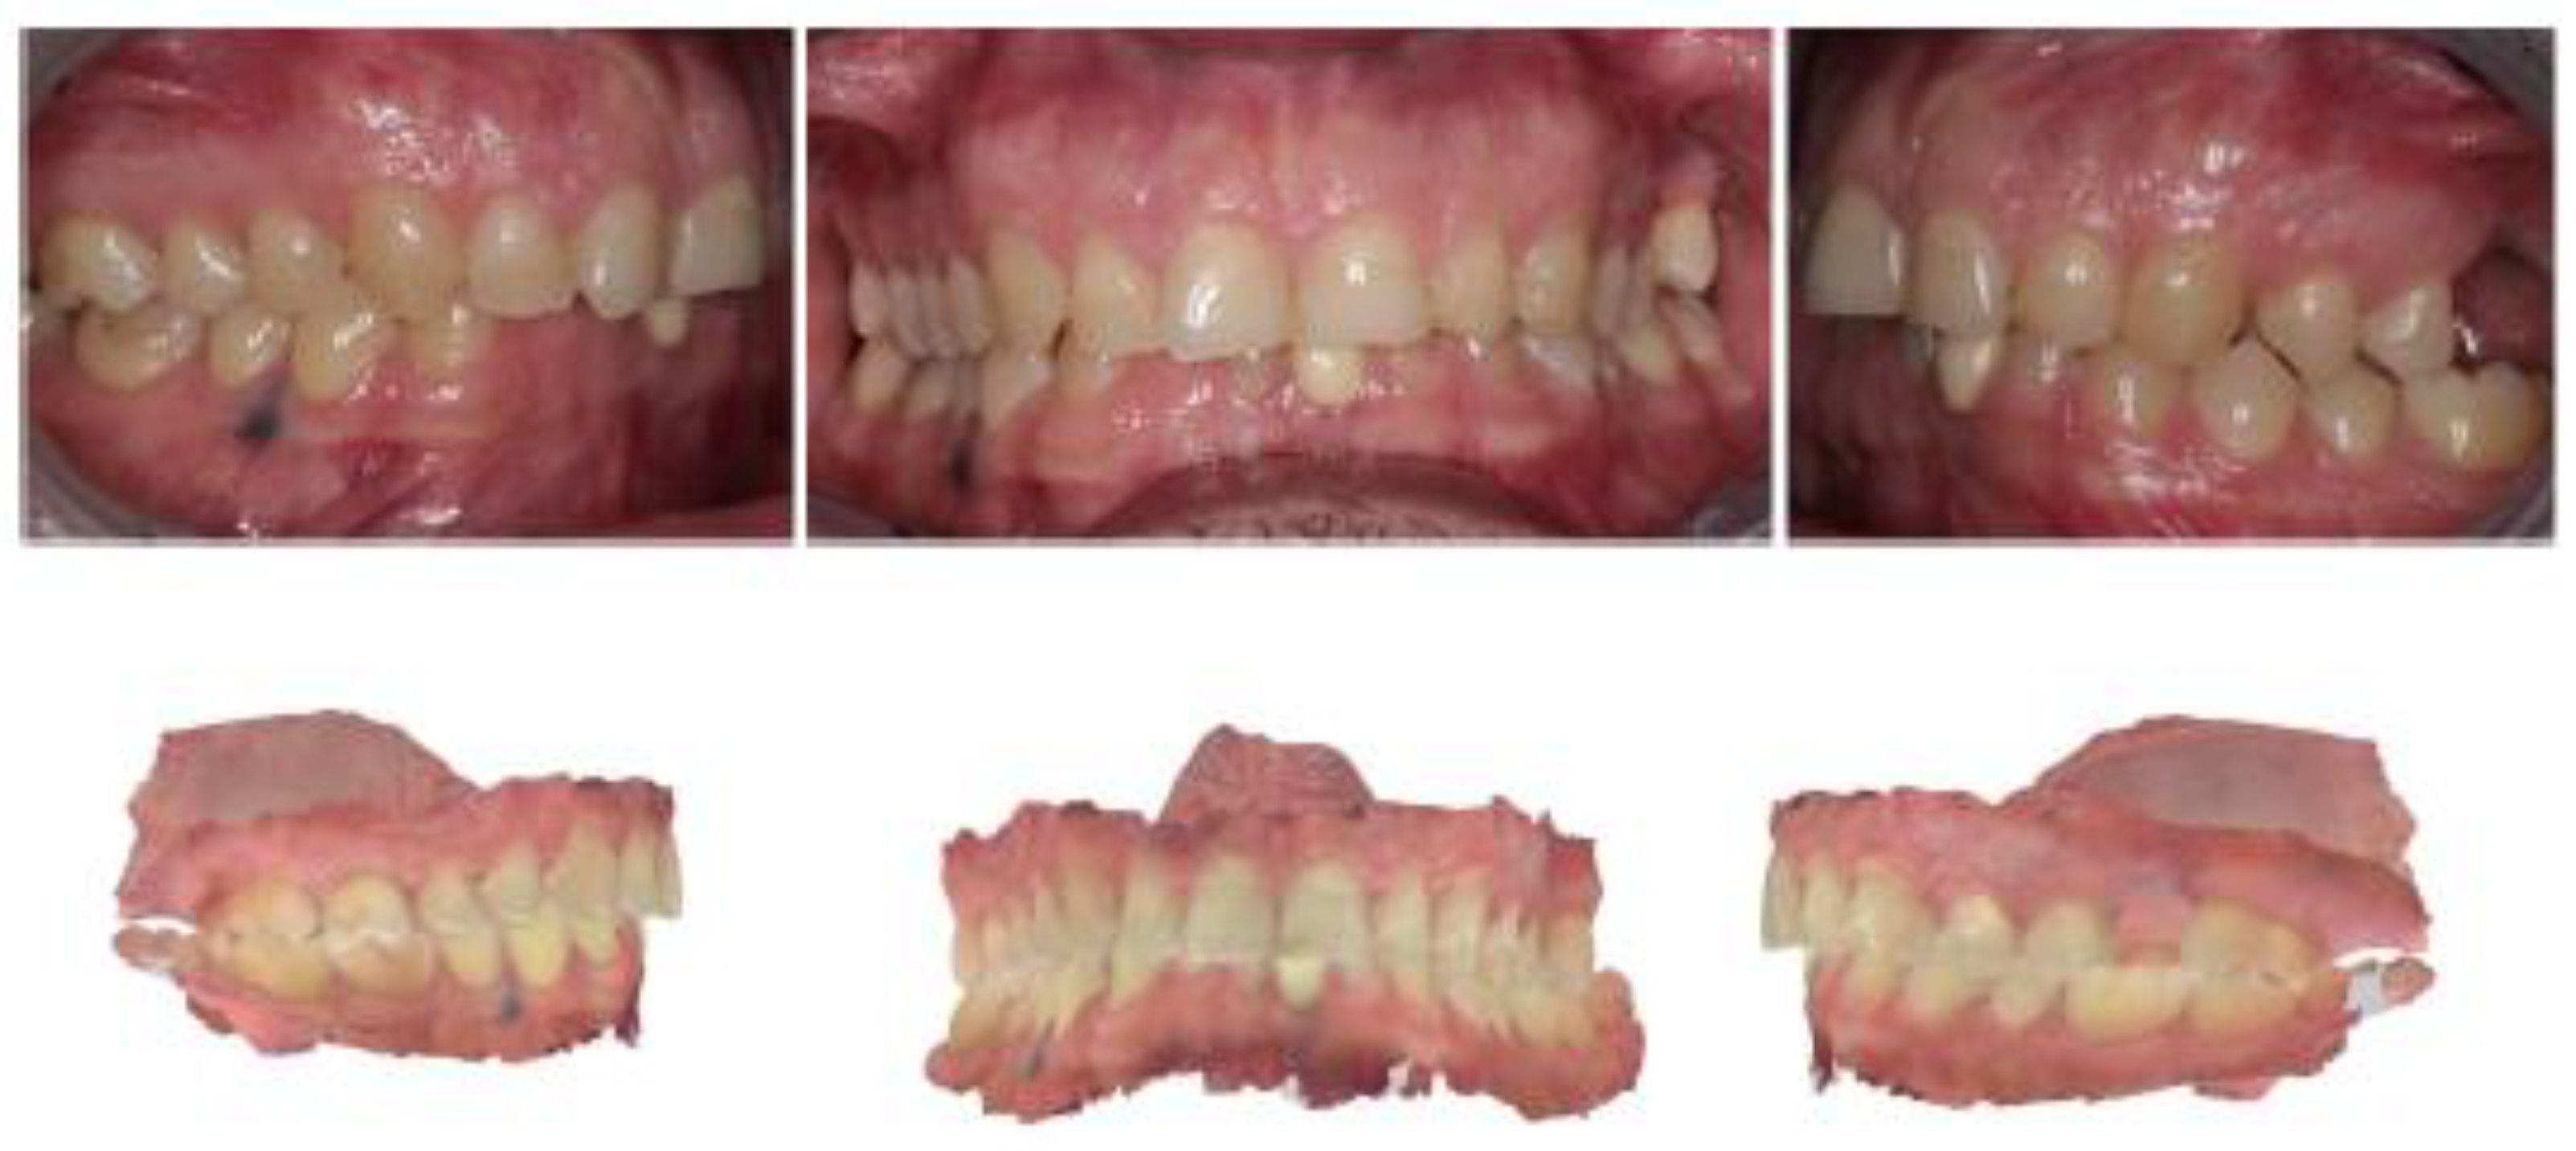

Intraoral occlusal relationships are shown in Figure 16.

Figure 16. Intraoral photos and intraoral scans show occlusal relationships: class I molar on the right and left and lower midline deviated to the right compared with the upper.